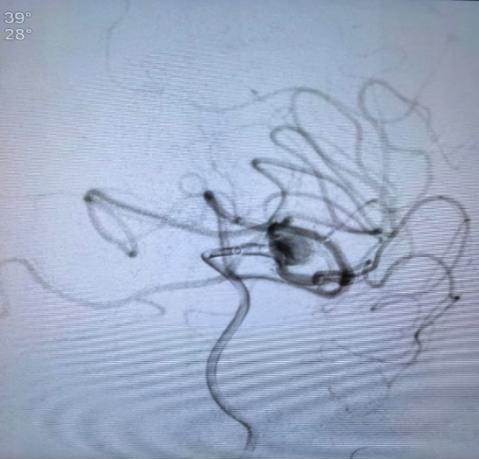

6月17日,山东第一医科大学第三附属医院神经内科团队在麻醉手术科、微创介入科等多科室的紧密协作下,成功完成了神经内科首例瘤内扰流装置(WEB)治疗复杂颅内动脉瘤的手术,术后患者恢复良好。手术的成功开展标志着医院在复杂性脑动脉瘤介入治疗领域取得了重要突破。

本例患者病情极具挑战性:动脉瘤位于左侧大脑中动脉分叉部,瘤体较大(11.2mmx9.1mm)且有两个子瘤,破裂出血的风险非常高。更为棘手的是,从瘤体上直接发出两条重要的分支血管,这类宽颈、分叶状且累及重要分支的动脉瘤,若采用传统的支架辅助弹簧圈栓塞技术,不仅耗时长(2-3小时),而且操作过程极具挑战性,面临着非常高的分支闭塞、术中出血等风险。

针对这一复杂困难病例,山东第一医科大学校副校长(副院长)、山东第一医科大学第三附属医院院长辛涛,科主任李振带领团队经过严谨评估,决定采用创新的WEB装置技术。WEB装置是一种自膨式、编织结构的球形栓塞植入物,其独特的设计理念在于通过“扰流”改变瘤颈口血流动力学,促使瘤腔内血栓形成,最终达到治愈目的。相较于传统方法,WEB技术具有操作更高效、精准定位、显著降低术中操作风险及围手术期并发症发生率的优势。

手术在李振的操作下顺利进行,WEB装置被精准输送到预定位置,有效覆盖了瘤颈并保护了分支血管,即刻造影显示瘤腔内血流明显减缓。整个手术过程不到二十分钟,患者术后恢复良好。